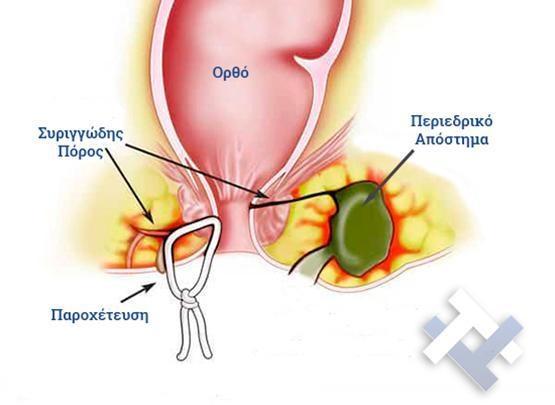

Ο Γενικός Χειρουργός Λιάγκος Γεώργιος MD PhD εκτελεί τις επεμβάσεις Λαπαροσκοπικά, Ενδοσκοπικά, Ανοιχτά Ελάχιστα Επεμβατικά και με Laser. Η θεραπεία εξατομικεύεται σε κάθε ασθενή ανάλογα με τις ανάγκες του. Αναλαμβάνει περιπτώσεις όπως κήλες και κοιλιοκήλες (αντιμετώπιση βουβωνοκήλης, αντιμετώπιση ομφαλοκήλης, θεραπεία επιγαστρικής κήλης, κήλη των αθλητών (Σύνδρομο κοιλιακών προσαγωγών), αντιμετώπιση μετεγχειρητικής κήλης, θεραπεία Μηροκήλης), πέτρες στη χοληδόχο κύστη, λαπαροσκοπική χολοκυστεκτομή, αντιμετώπιση Κύστη Κόκκυγος με λέιζερ (laser), παθήσεις πρωκτού, χειρουργική laser σύγχρονων κυκλικών ινών (αιμορροΐδες αντιμετώπιση, θεραπεία αιμορροϊδων με laser (LHP), αφαίρεση αιμορροΐδων με υπερήχους (HALL-RAR), χωρίς Χειρουργείο με ελαστικούς δακτυλίους (Τεχνική BARON-RBL), θεραπεία ραγάδας πρωκτού (Ραγάδα δακτυλίου), θεραπεία περιεδρικού συριγγίου, θεραπεία περιεδρικού αποστήματος, κονδυλώματα πρωκτού Θεραπεία, δερματικό ράκος (Skin tag) εκτομή, αντιμετώπιση Kνησμού, καρκίνος πρωκτού θεραπεία), παθήσεις Δέρματος, χειρουργική με laser CO2, αφαίρεση μορφωμάτων δέρματος - βιοψίες, αφαίρεση ελιάς (Σπίλου), σμηγματογόνος κύστης θεραπεία, αφαίρεση λιπώματος, είσφρυση όνυχος χειρουργείο, καρκίνος δέρματος θεραπεία, οξεία σκωληκοειδίτιδα, παθήσεις Λεπτού και Παχέος Εντέρου, ειλεός λεπτού εντέρου, εκκολπωμάτωση (Εκκολπωματίτιδα) σιγμοειδούς, καρκίνος παχέος εντέου, κολοστομίες, port χημειοθεραπείας κ.α. εξυπηρετώντας Παγκράτι και γύρω περιοχές.